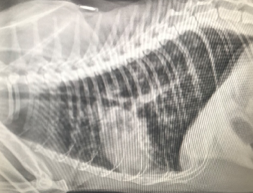

(3) Thoracic radiographs

Why? Thoracic radiographs depict Sparta’s heart and lungs. The size of the heart can be measured; an enlarged heart size suggests disease. The appearance of the lungs on the radiograph can help us pinpoint where the problem is in the lungs and what it may be.

Results: Sparta’s heart was a normal size, but there was material in and surrounding the bronchi and bronchioles of his lungs. This material was plugging up his airways and preventing the passage of air into his lungs. His lungs were also hyperinflated, which was a consequence of trying to overcome the obstruction to breathe.

Sparta. The small white circles throughout his lungs are the inflamed small airways.